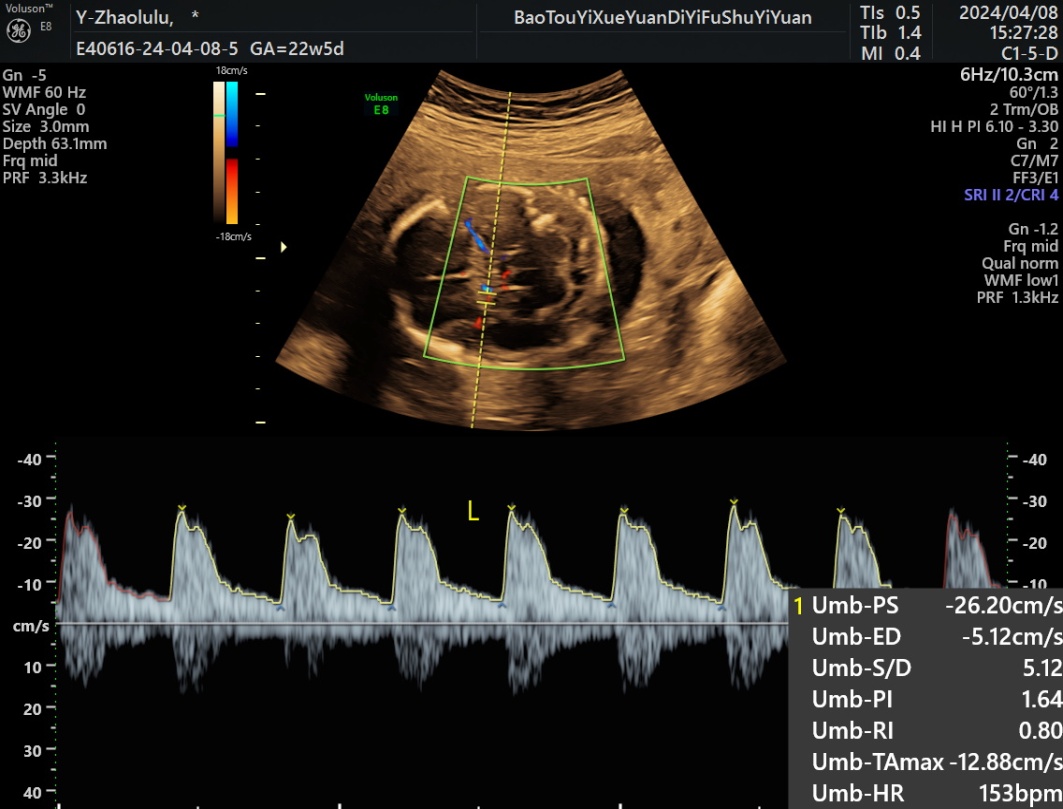

1) 200例胎儿UA、MCA、RA、UtA多普勒全部都被记录(图1图2)其中20~23周50胎,24~27周50胎,28~31周50胎,32~36周50胎,不同孕周血流参数测量值见表1~4

Figure 2. Left MCA spectrum of normal fetus at 22w5d of pregnancy

2. 孕22w5d正常胎儿左侧MCA频谱图